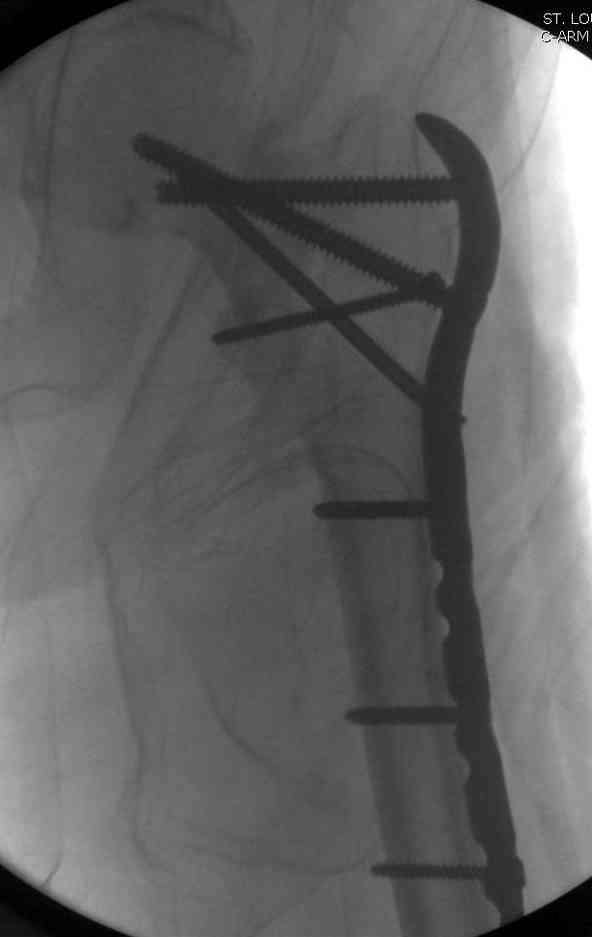

23.08.07г. на форуме был представлен больной 68 лет с диагнозом: несросшийся подвертельный косой перелом. http://www.weborto.net/forum/1187804790/ Больной после неудачной операции в одном районе в течении 7 месяцев был прикован к постели, с пролежнями в обл. крестца. Больной в течении 10 дней подготовлен к операции, НВ-153, эритр.-4,5, соэ-7, ВСК-3-3,40. ПТИ-81.ФНГ-3100. Мочевина, билирубин, АЛТ,АСТ в пределах нормы. Для остеосинтеза готовили пластину клинковую, штопор Сиваша . Во время операции дистальный отломок легко мобилизовали, проксимальный отломок был ротирован и сильно приведен медиально( m. iliopsoas), а также сильно замурован плотной как хрящ рубцовой тканью. Линия излома косая около 10 см., наружная стенка большого вертеля почти не было. У малого вертеля отсекли сухожилие m. iliopsoas и дальше на глубине начали распатором мобилизовать конец проксимального отломка, который был сильно приведен и находился глубоко , когда начали отделять изогнутом распатором заднюю часть конца и чуть подтянут отломка и тут начался сильнейшая кровотечения, фонтаном, найти сосуд и остановить кровотечение в ране не удалось, сосуд вместо с рубцовой тканью ушел назад и медиально отломка. Срочно рану туго тампонировали и остановили кровотечение, вызвали сосудистого хирурга,но их не нашли, оказалась один в отпуске, двое на экстренном вызове в районах. Передным доступом (по L. vasorum ) обнажали бедренную артерию, провели резиновую держальку и временно сосуд зажали, открыли рану , убрали тампон, но на глубине в толще рубцовых тканей поврежденный сосуд найти не удаётся. Поэтому переднюю рану расширили вниз, при ревизии бедренная артерия не повреждена, а глубокая бедренная артерия повреждена пристеночно, примерно на 2-3см от место отхождения от бедренной артерии, не доходя до ответвлений на огибаюших артерий. А одноимённая вена повреждена на протяжении около 3х см, и в данный момент восстановить не удается и пришлось перевязать оба конца, на артерию наложили поперечный сосудистый шов, бедренную артерию освободили, кровоток восстановился. Но теперь начала вся рана кровить! Венозный застой! К этому времени состояние больного резко ухудшилось, наступил клинический смерть, с трудом реанимировали, вроде б и кровотечение остановилось, как а/д подняли до 100/60мм опять начался кровотечение, коагулятором остановить не удаётся, рану туго тампонировали, перелито больше одного литра эр. массы и плазмы,и ешё кровозаменители, стабизол, рефортан и др. а/д держим 90/60, интесивная терапия против ДВС синдрома. Реаниматологи не разрешают производить остеосинтез, так как гемодинамика нестабильная , держиться под вазопрессорами. Через час состояние больного не улучшается , реаниматологи дали 10 минут и мы быстро кое как репонировали, остеосинтез продолной пластиной ЦИТО, но шурупы в проксимальном отломке плохо держутся, (остеопороз ), но другого выхода не было, для клинковой пластини просто небыло времени. Тканевое и капиллярное кровотечение продолжается, рану туго тампонировали и наводяшие швы на рану. Наложили гипсовой сапожок с деротатором. Больной находился в общей реанимационной отд. 20 дней и вышел из критического состояния. Но на контр. Р-грамме шурупы как и предпологали не держались, имеется ротация проксимального отломка, хотя ось бедра правильная и клинически деформации нет, даже определяется клиническая схватка . Я долго думал, вынести это на форум или нет, позвонил Челнокову А Н, он сказал <надо быть честным до конца, доложил на форуме, надо сообшить и о резултатах> Уважаемые коллеги! Какие были допушены ошибки? И какие рекомендации будут теперь? . P. S. за некачественный р-снимок прошу прошения!

Адекватная фиксация достигается длинным 95 градусным Blade Plate, где клинок пластины, связывая головку со средней трети бедра, создал бы условия для сращения.

Другой вариант пластины, это Synthes Proximal Locking Plate предназначенный для лечения прксимальных переломов бедра, где три шурупа: два 7.3 мм, введенных в головку под углом 95, 120 и 5.0 мм в 130 градусов, создают угловую стабильность.

Профилактику прорезывания шурупов в кости можно добиться введением в отверстие цемента, потом проведением шурупа, цемент, застывая, удерживает шуруп в правильном положении.